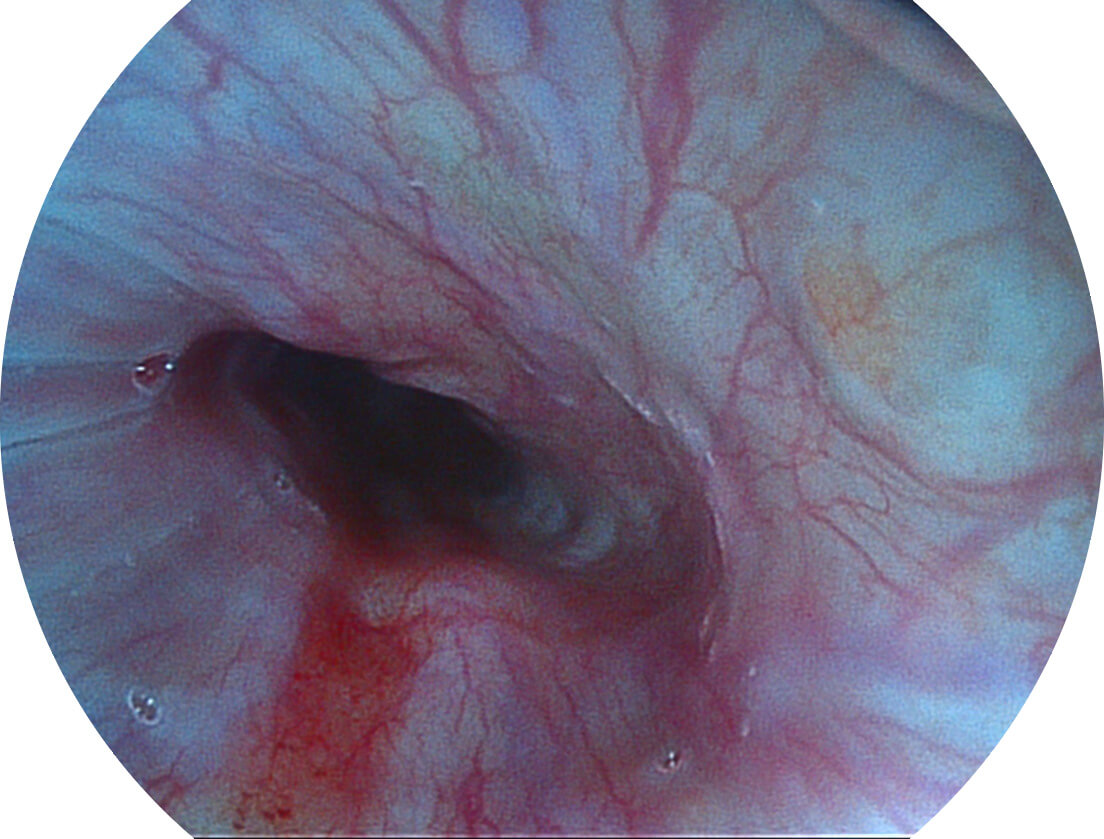

Spectral Focused lmaging, SFI

图像具有高亮度、高黏膜血管颜色对比度的特点,且不改变粘液、食物残渣、粪便的基本颜色,可在中远景下进行观察,助力消化道早期疾病的诊断。

白光图像

SFI图像